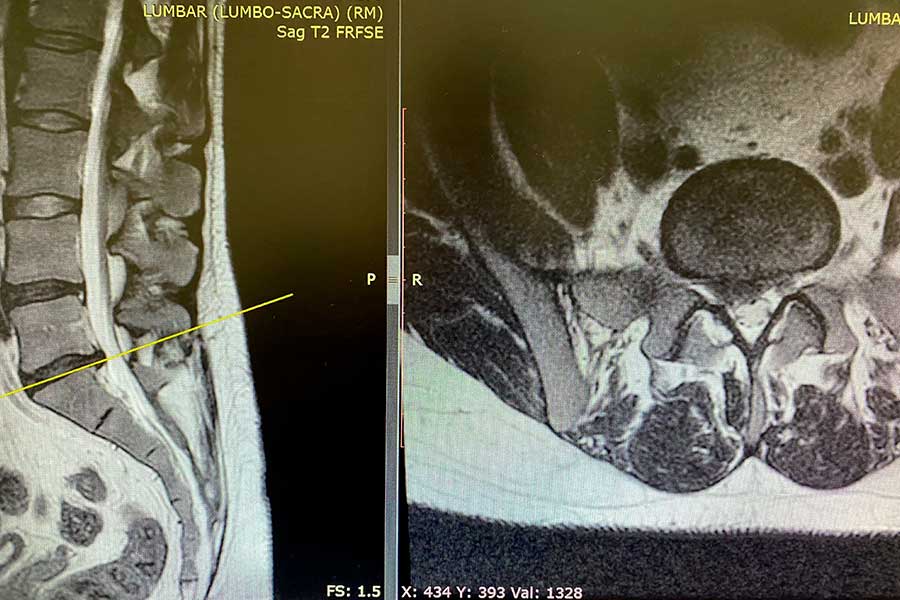

En esta ocasión, encontramos una cirugía de columna de un paciente de 33 años que acude a consulta con una ciática derecha, con un dolor persistente que se extiende hasta la planta del pie y le dificulta considerablemente las actividades diarias.

Tras un estudio médico completo, tanto a nivel radiológico como clínico, se observa un problema de naturaleza mecánica, por lo que el tratamiento médico conservador queda descartado y se opta por realizar una intervención.

El dolor del paciente procede de una hernia cervical, la cual habrá que localizar y extraer mediante endoscopia mínimamente invasiva.